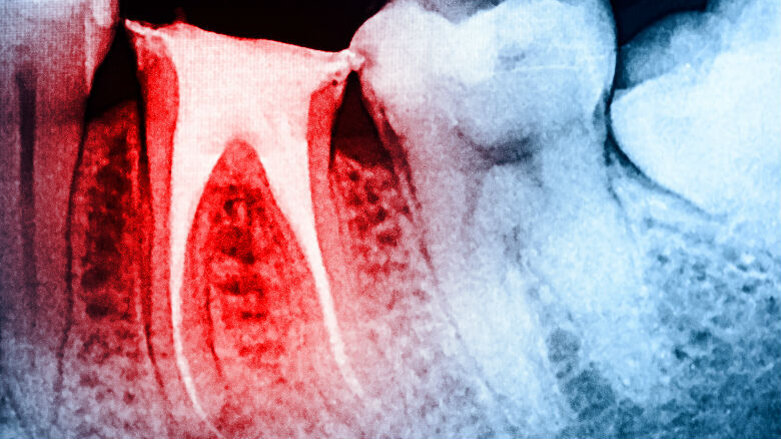

Rigenerazione del complesso polpa-dentina, gestione del dolore, procedimenti velocizzabili, soluzioni ricostruttive: è rappresentato tutto il percorso di cura dell’endodonzia contemporanea nella sessione di endodonzia che caratterizza il “percorso giallo” al X congresso Internazionale di Associazione Italiana Odontoiatri, in programma dal 13 al 15 giugno al Centro Congressi di Chia.

In programma dalle 9 alle 18 di giovedì 13 giugno, il corso – unico accreditato con 8 crediti Ecm – è moderato dalle professoresse Elisabetta Cotti di Cagliari e Denise Irene Karin Pontoriero di Genova. Protagonista, innanzitutto, Ken Hargreaves Direttore del Dipartimento di Endodonzia all’Università del Texas (San Antonio), autore di oltre 160 articoli che nella sua lezione su endodonzia rigenerativa e gestione del dolore tratterà di come salvare i denti rigenerando il complesso polpa-dentina e descriverà lo stato attuale delle procedure endodontiche rigenerative, il loro potenziale e i predittori del successo di guarigione. Hargreaves approfondirà inoltre la gestione efficace del dolore dentale acuto selezionando la migliore combinazione di analgesici. Saranno fornite le ultime informazioni su FANS, analgesici con paracetamolo e anestetici locali: obiettivo, avere un’applicazione immediata per la successiva emergenza del paziente.

Secondo nome forte della giornata è Fabio Gorni titolare d’insegnamento in Estetica periorale Università Vita Salute San Raffaele a Milano e socio attivo della Società Italiana di Endodonzia, autore dell’opera multimediale il “Recupero endodontico dei denti gravemente compromessi” della collana Medtutor (Utet 2008). Il senso della lezione: nel contemperare i concetti biologici che da sempre guidano i trattamenti endodontici con la mini invasività serve un equilibrio altrimenti si rischia un risultato terapeutico non ottimale. La valutazione coinvolge diagnosi radiologica, rivisitazione degli accessi cavitari, tecniche endodontiche e strumentario. Il poter eseguire in modo completamente meccanico la sagomatura è un vantaggio enorme sia nel ridurre i tempi di lavoro sia nel migliorare il risultato finale. E dopo l’endo… servono restauri adatti. Sandro Pradella, libero professionista a Curtatone (Mantova) e docente a contratto di Conservativa a Parma parlerà di soluzioni restaurative indirette nei denti anteriori discolorati da trattamento endodontico. I restauri con materiali metal-free hanno subito negli ultimi anni un notevole sviluppo grazie all’ottima integrazione estetica finale e alla validità della cementazione adesiva; rovescio della medaglia è la loro traslucenza, che obbliga il clinico già in fase progettuale a tener conto di eventuali decolorazioni presenti nel dente da restaurare. La ricostruzione di denti che possono aver subito uno scorretto trattamento endodontico andrà fatta con materiali idonei per ottenere un moncone di un colore simile alla dentina del dente naturale. Infine la cementazione del manufatto dovrà prevedere cementi con diverse colorazioni che consentano un’ottima integrazione mimetica finale. La relazione esaminerà i vari fattori negativi e presenterà una serie di soluzioni restaurative.